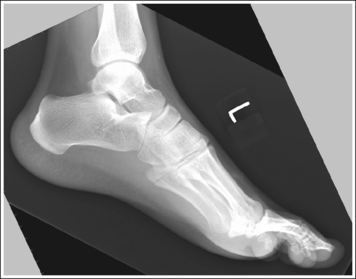

The foot is in a lateral projection. The talar domes are superimposed, the tibiotalar joint is open, and the distal fibula is superimposed by the posterior half of the distal tibia.

• Talar domes. The domes of the talus are formed by the most medial and lateral aspects of the talar's trochlear surface. On a lateral foot projection, they appear as domed structures that articulate with the tibia. On a properly positioned lateral foot projection, the talar domes should be superimposed and appear as one and the tibiotalar joint should be open. When the lateral foot is mispositioned, the domes are individually demonstrated, and they obscure the tibiotalar joint. Proximal-distal misalignment of the domes results from poor knee and lower leg positioning, and AP misalignment of the domes results from poor foot positioning.

• Effect of foot positioning on AP talar dome superimposition. To demonstrate accurate AP alignment of the talar domes, position the lateral surface of the foot parallel with the IR. If this surface is not parallel with the IR, one of the talar domes is demonstrated anterior to the other. When the leg is rotated more than needed to place the lateral foot surface parallel with the IR, as shown in Figure 6-29, the medial talar dome is demonstrated anterior to the lateral talar dome (see Image 20). If the leg is not rotated enough to place the lateral foot surface parallel with the IR, as shown in Figure 6-30, the medial talar dome is demonstrated posterior to the lateral talar dome (see Image 21).

When viewing a lateral foot projection that demonstrates one of the talar domes anterior to the other, evaluate the position of the fibula in relation to the tibia to determine how to reposition the patient. On most lateral foot projections with accurate positioning, the fibula is positioned in the posterior half of the tibia. If the fibula is demonstrated more posteriorly than this relationship on a lateral foot projection with poor positioning, the medial talar dome is anterior and the patient was positioned with the forefoot depressed and the heel elevated (leg externally rotated), as shown in Figure 6-29. If the fibula is demonstrated more anteriorly than this relationship, the medial talar dome is posterior and the patient was positioned with the forefoot elevated and the heel depressed (leg internal rotation), as shown in Figure 6-30.

A standing lateromedial foot projection is accomplished by placing the IR against the medial aspect of the foot and aligning the lateral foot surface parallel with the IR, as shown in Figure 6-32. Even pressure should be applied to both feet. Notice that the patient's heel is situated slightly away from the IR when the lateral foot surface is parallel with the IR. The resulting image should meet all the analysis requirements listed for the mediolateral projection.

The most common misposition for the standing lateromedial projection of the foot shows the medial talar dome positioned anterior to the lateral talar dome and the distal fibula positioned too posteriorly on the tibia (see Image 20). This misposition is a result of aligning the medial foot surface parallel with the IR, as shown in Figure 6-33, rather than the lateral surface. When such an image is obtained, move the patient's heel away from the IR (leg internally rotated).